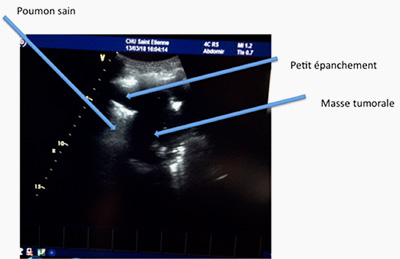

Grâce aux ultrasons, l’exploration de la plèvre se fait sans irradiation ni geste invasif. On peut déceler les pneumothorax (air dans la plèvre), les pleurésies (liquide dans la plèvre) (photo 11) ou repérer une masse ou un nodule pulmonaire au contact de la plèvre (photo 12)

Ensuite on peut réaliser une ponction très précise grâce au guidage de l’échographie